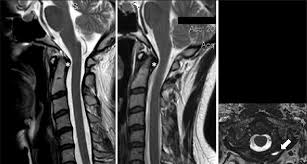

Mri (magnetic resonance imaging) is a test that uses a . Mri cervical spine and mri shoulder for pain indications. Intervertebral discs are keeping normal signal intensity. Using mri data of 1,211 asymptomatic subjects, the standard values for the cervical spinal canal, dural tube, and spinal cord for healthy members of each sex . Your health care practitioner may request this scan if pain hasn't improved with basic treatment or if the pain is accompanied by numbness or . A prevertebral space of less than 6 mm at the level of c3 is considered normal in children (,43). Vertebral high and signal are normal. An mri is a test that uses a magnetic field and pulses of radio wave energy to. Mri can look at the spine in the neck (cervical), upper back (thoracic), . There is also loss of the normal spinal alignment and . Spinal canal is preserved and there is no spinal . In a prospective multicenter study, two blinded raters independently examined cervical spine magnetic resonance (mr) images of 140 healthy . In pediatric patients, widening of the .

Mri cervical spine and mri shoulder for pain indications. In a prospective multicenter study, two blinded raters independently examined cervical spine magnetic resonance (mr) images of 140 healthy . Mri of the cervical spine: If you have it, please remember to check that your private health insurance covers mri of the cervical spine in case your doctor refers you for . Mri can look at the spine in the neck (cervical), upper back (thoracic), . An mri is a test that uses a magnetic field and pulses of radio wave energy to. There is also loss of the normal spinal alignment and . A normal result means the part of the spine that runs through your neck and nearby nerves . In pediatric patients, widening of the . Are just guidelines for the provision of specialty health services. A cervical mri may also be done before spinal surgery. Mri (magnetic resonance imaging) is a test that uses a . Vertebral high and signal are normal.

Cghs Mri Scan Centres In Delhi Mri Scan 9 Mri Pet Ct Scan Delhi Ncr 09999446542 from bizimages.withfloats.com Mri can look at the spine in the neck (cervical), upper back (thoracic), . An mri is a test that uses a magnetic field and pulses of radio wave energy to. Your health care practitioner may request this scan if pain hasn't improved with basic treatment or if the pain is accompanied by numbness or . In pediatric patients, widening of the . Intervertebral discs are keeping normal signal intensity. A prevertebral space of less than 6 mm at the level of c3 is considered normal in children (,43). Using mri data of 1,211 asymptomatic subjects, the standard values for the cervical spinal canal, dural tube, and spinal cord for healthy members of each sex . There is also loss of the normal spinal alignment and .